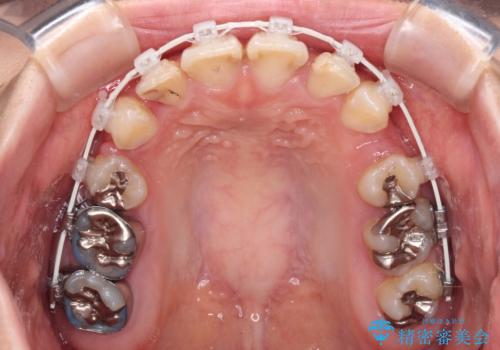

- 上の前歯の出っ歯とでこぼこの歯並びを気にして来院された患者様です。

上下顎歯列ともに前方に突出していましたが、上顎歯列がより前方位にあったため、上顎左右は第1小臼歯を、下顎左右は第二小臼歯を抜歯することとしました。

目立たないワイヤー装置にて抜歯矯正を行うこととしました。